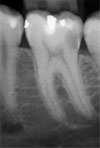

3. Высокое качество снимков: Heliodent Vario позволяет получить высочайшее качество изображения при минимальной дозе облучения.

Минимальное время экспозиции (0.03-3.2 с. для плёнок и датчиков любой чувствительности)

5.Два режима съёмки: Heliodent Vario иммет два режима съёмки - плёночный и цифровой с помощью системы Sidexis. Для прехода из одного режима в другой достаточно одного нажатия на кнопку.

2. Цифровой визиограф SIDEXIS с минимальной дозой облучения

Предназначен для получения рентгеновских снимков зубов с помощью датчика и сохранения их в компьютере. Состоит из: